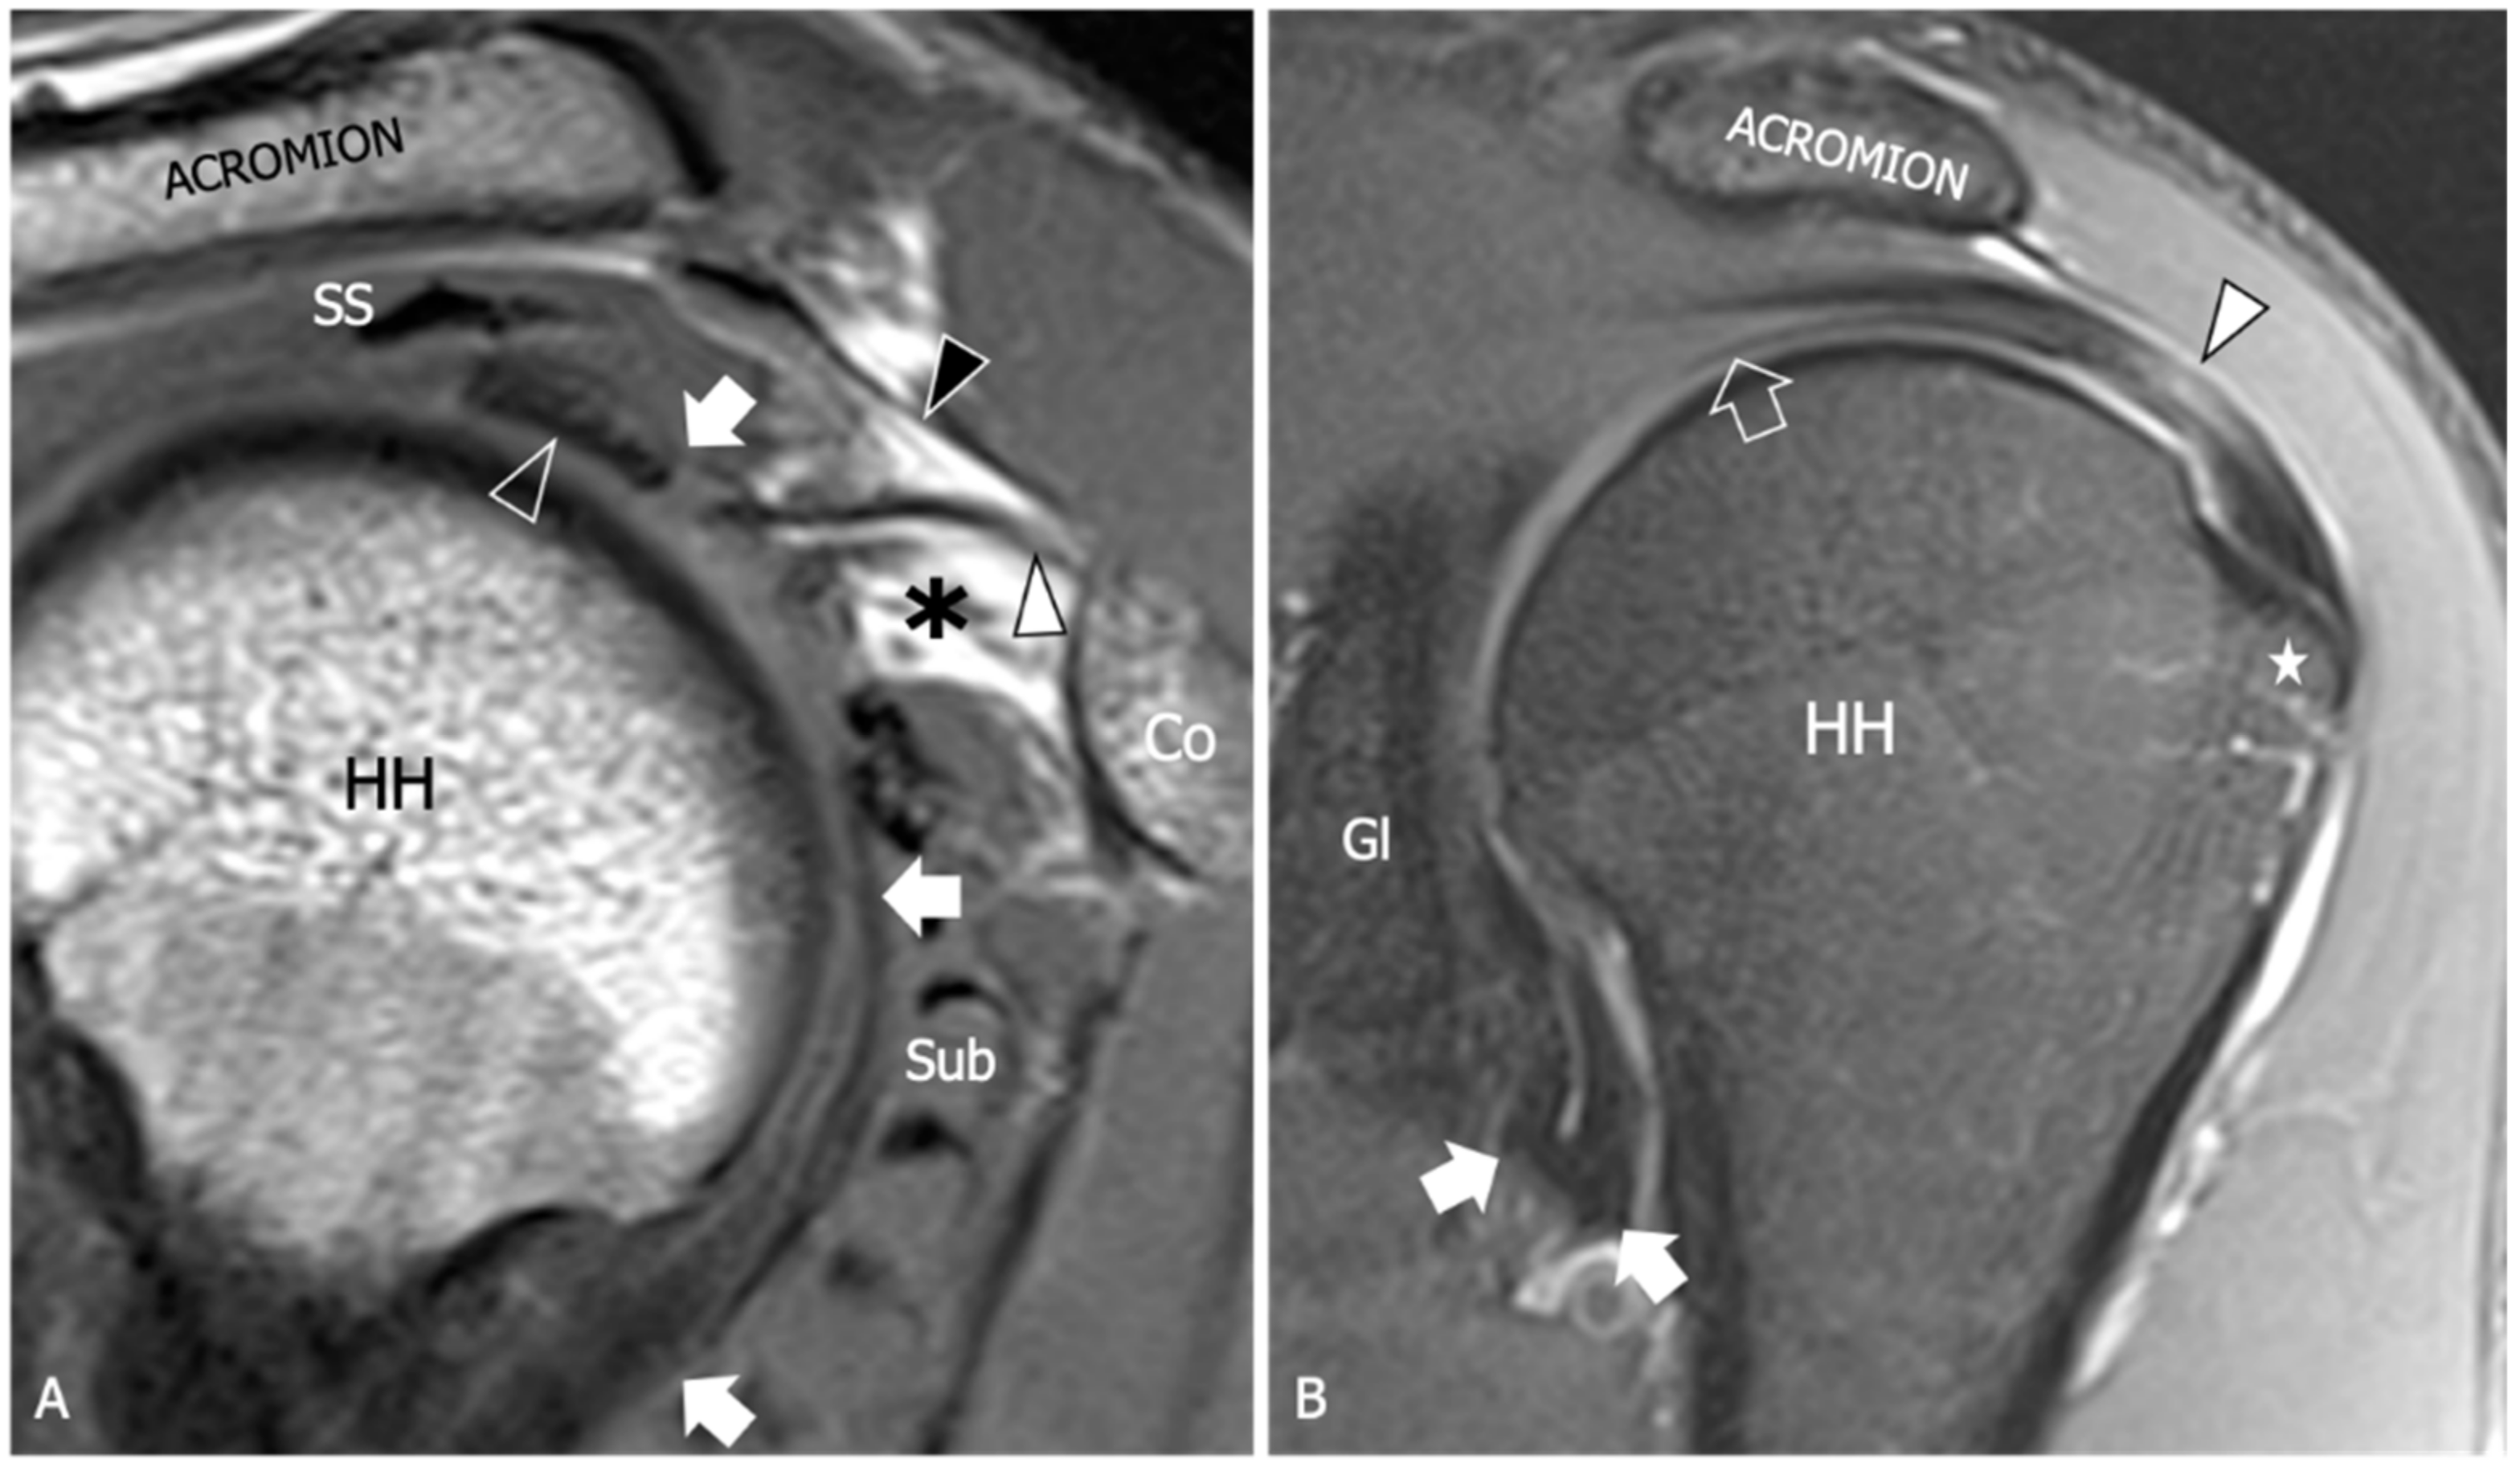

Figure 3.

Adhesive capsulitis, spectrum of MRI findings. (A) Sagittal tSE T1-weighted MRI scan from a 42 year old woman with a three-month history of shoulder pain demonstrates mild thickening of the coracohumeral ligament (white arrowhead) and initial effacement of the subcoracoid fat triangle (asterisk) by hypointense synovium. Black arrowhead, coracoacromial ligament. (B) Coronal tSE Proton Density MRI scan from a 68 year old woman with recent onset of pain and progressive limitation of glenohumeral ROM shows a marked thickening of the inferior capsule (arrows), which appears edematous and demonstrates increased signal intensity in fluid-sensitive sequences. (C) Sagittal tSE T1-weighted and (D) Sagittal tSE fat-suppressed T2-weighted MRI images from a 70 year old male with a one-year history of severe limitation of active and passive shoulder motion demonstrate complete obliteration of the subcoracoid fat triangle by synovial tissue (arrows), which is also extended underneath the long head of the biceps tendon (arrowhead) in the area of the pulley (asterisk). The coracohumeral ligament appears embedded by the synovium. Note severe thickening and hyperintensity of the anteroinferior capsule (outlined arrowhead). Ac, acromion; Cl, clavicle; Co, coracoid; SS, supraspinatus; Sub, subscapularis; GL, scapular glenoid; HH, humeral head.

The thickening of the rotator interval and coracohumeral ligament are considered specific signs, although poorly sensitive, of AC. Various cut-off points were proposed in the past, and the optimal value is still a matter of debate. Mengiardi et al. found that a rotator interval capsule thickness ≥7 mm had a specificity of 86% but only a sensitivity of 64% [54]. Similarly, they reported that a coracohumeral ligament thickness ≥4 mm had high specificity (95%) but lower sensitivity (59%). In another study by Jung et al., it was suggested that a rotator interval thickening of over 6 mm on sagittal oblique proton-density images may correlate with the patient’s range of rotational motion [55]. Synovial proliferation around the rotator interval can be observed as capsule thickening with intermediate to low T1 signal intensity, hyperintense signal on fluid-sensitive sequences, and enhancement after contrast administration. While the synovial obliteration of the triangular fat pad inferior to the coracohumeral ligament has been identified as a sign with high specificity (100%), its sensitivity remains poor (32%) [54]. Referred to as the “subcoracoid triangle sign”, the obliteration of the subcoracoid fat pad has been more frequently observed in early clinical stages 1 and 2 of AC [56]. The visibility of this sign is optimal on sagittal oblique images and can be easily evaluated using conventional MRI techniques, where it appears hypointense relative to subcutaneous fat on T1-weighted images.

Several research studies have shown that hyperintensity and thickening of the inferior shoulder capsule are indicative of AC. In particular, hyperintensity in the axillary pouch/inferior glenohumeral ligament complex on MRI using non-arthrography T2-weighted fat-suppressed sequences demonstrated high sensitivity (85.3–88.2%) and specificity (88.2%), and low variability among different observers with a kappa value of 0.85 [57]. Regarding inferior capsule thickness, a first MRI study with a limited number of participants evidenced that when the measurements of the joint capsule in the axillary recess exceed 4 mm on T1 oblique coronal MR images, it suggests the diagnosis of AC with a sensitivity of 70% and a specificity of 95% [58]. In Jung et al.’s study, performed with conventional MRI, a threshold value of 4.5 mm in axillary recess capsule thickness measured on T1 oblique coronal images demonstrated the greatest diagnostic accuracy for AC, with a sensitivity, specificity, and overall accuracy of 91%, 90%, and 90%, respectively [55]. Other studies have shown that the thickness of the axillary recess is related to the clinical stage. Sofka et al. found a mean axillary pouch thickness of 7.5 mm for stage 2, also demonstrating a statistically significant correlation between the hyperintense signal of the capsule on proton density sequences obtained with conventional MRI and this clinical stage [56]. Contrary to the claim that MRA may have some advantages in measuring inferior capsular thickness, it is important to consider potential risks and complications associated with this technique, including hemorrhage and septic arthritis. Moreover, the sensitivity and specificity of inferior glenohumeral thickening on MRI were not significantly different from those on direct MRA found in a recent meta-analysis [52]. Overall, despite the potential of MRA in disclosing ancillary findings, such as leakage of contrast agent anterior to the medial margin of the scapula, reduced distension of the axillary recess, pseudo-synovitis over the cranial border of the subscapularis tendon and the biceps anchor, and widening of the subscapular recess [1] (Figure 4), the intra-articular injection of contrast agents appears unjustified in patients with AC.